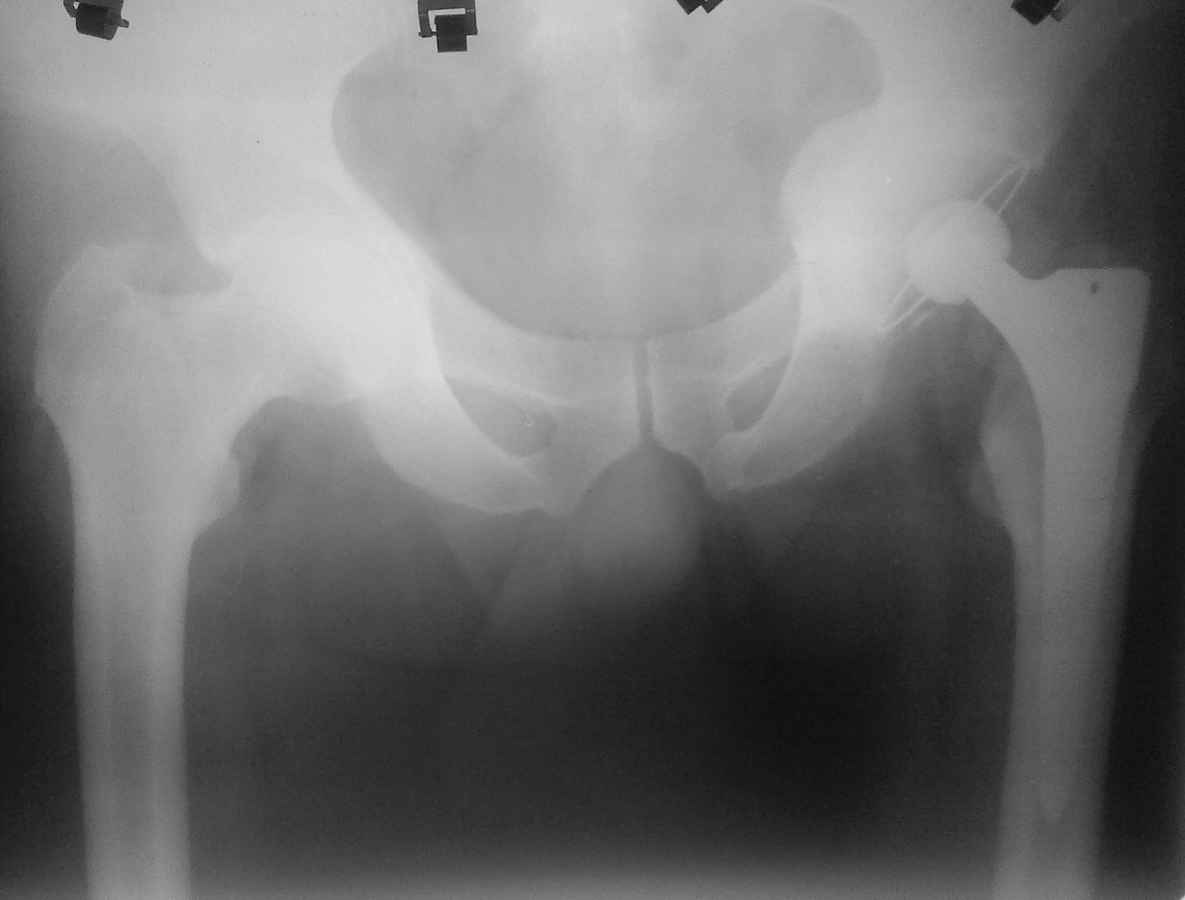

протрузионный коксартроз

Здравствуйте. Уважаемые коллеги, поделитесь опытом у кого какая тактика при протрузионных коксартрозах

У нас в клинике принято выполнять костную пластику дна стружкой из гололки, а потом цементную чашку (снимки прилагаю). Выскажите свои взгляды на эту проблему, пожалуйста.

мы делаем пластику чипсами из головки, затем press fit.

А почему цемент. Лучше бесцементную чашу в данном случае. А Рыков Хабаровск

согласен, в цемент вряд ли прорастет даже аутокость. а вот в какой-нибудь Porocoat возможно.